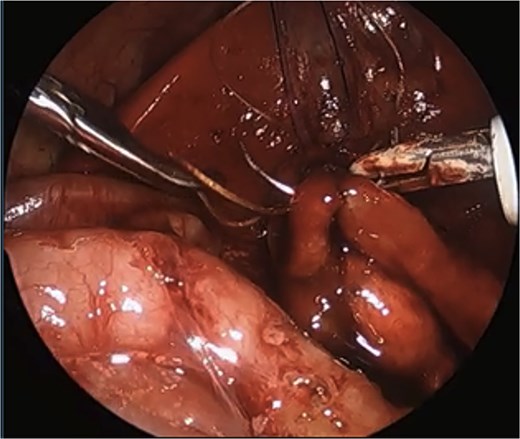

We describe a modification of the port placements during a laparoscopic duodenal atresia repair in a very low birthweight, preterm infant; however, these modifications can be used to optimize repair in any duodenal atresia patient. The modified positioning of the instruments allowed for a working space better triangulated for suturing with both hands at right angles to each other and allowed for the camera to be further away from the target tissue. These modified placements also enabled a more lateral approach, more in line with the rotation of the duodenum, and facilitated easier angles for laparoscopic suturing with a straight-on view of the anastomosis, overall increasing the safety of the procedure and limiting the risk of intraoperative complications (Fig. 4).

Laparoscopic view of anastomosis. The surgery was completed successfully laparoscopically, and the patient had no postoperative complications.